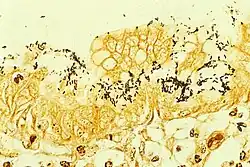

Micrograph of H. pylori colonizing the stomach lining

Chronic inflammation that is a feature of cancer development is characterized by infiltration of neutrophils and macrophages to the gastric epithelium, which favors the accumulation of pro-inflammatory cytokines, reactive oxygen species (ROS) and reactive nitrogen species (RNS) that cause DNA damage.[62] The oxidative DNA damage and levels of oxidative stress can be indicated by a biomarker, 8-oxo-dG.[62][63] Other damage to DNA includes double-strand breaks.[64]